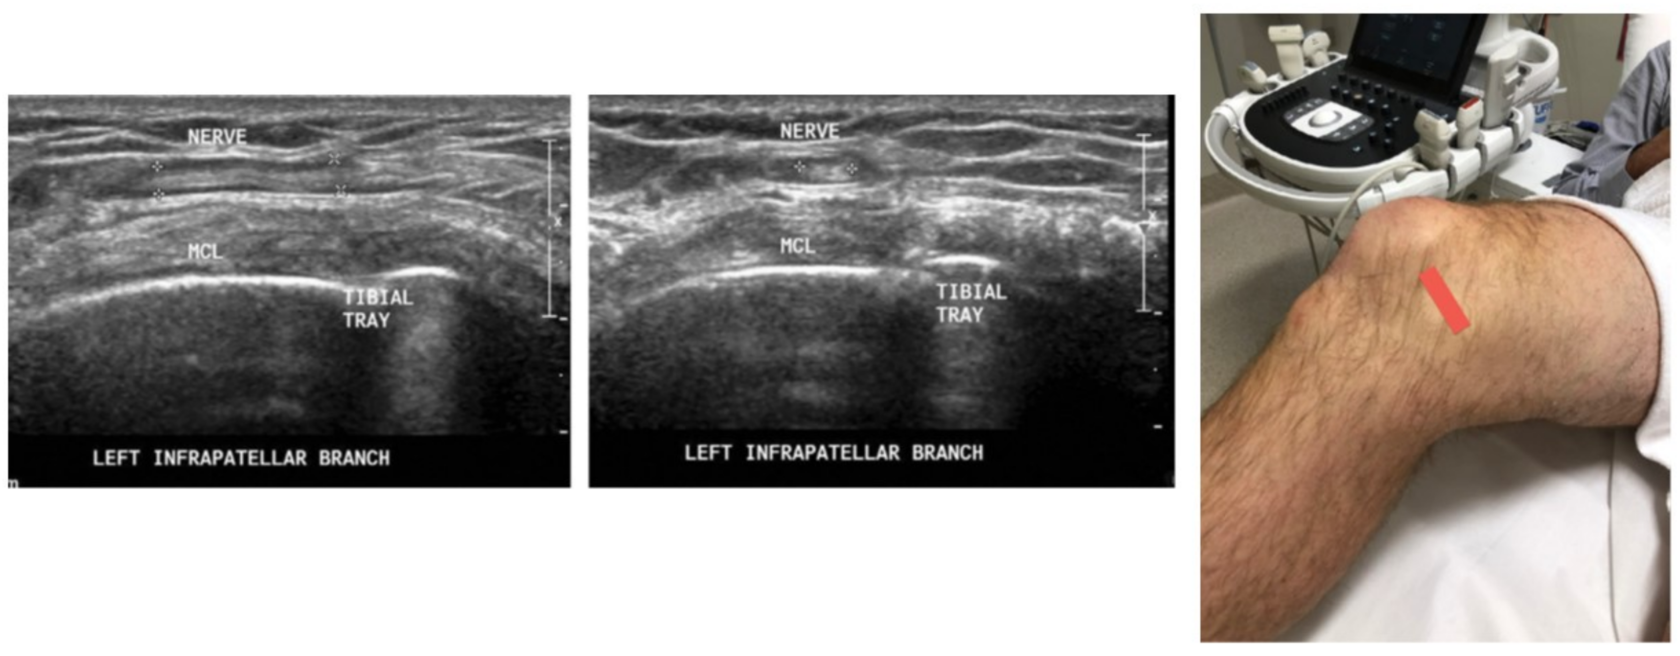

Криоанальгезия коленного сустава:

infrapatellar branch of the saphenous nerve

infrapatellar branch of the saphenous nerve (IBSN) and anterior femoral cutaneous nerve (AFCN)